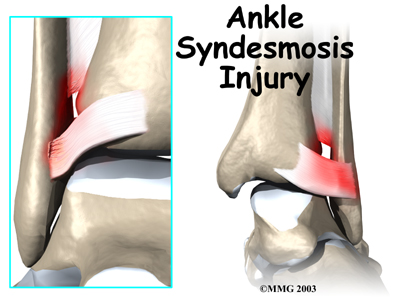

Ankle Syndesmosis Injuries

An ankle injury common to athletes is the ankle syndesmosis injury. This type of injury is sometimes called a high ankle sprain because it involves the ligaments above the ankle joint. In an ankle syndesmosis injury, at least one of the ligaments connecting the bottom ends of the tibia and fibula bones (the lower leg bones) is sprained. Recovering from even mild injuries of this type takes at least twice as long as from a typical ankle sprain.